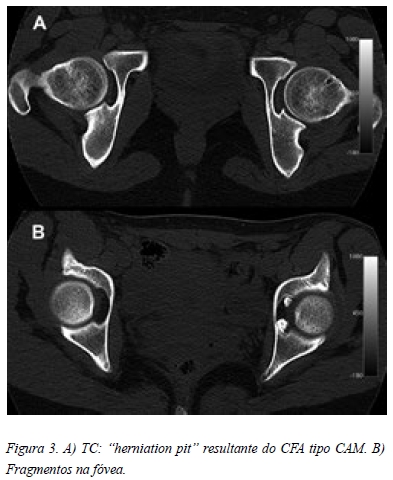

Na radiografia em incidência antero-posterior da bacia era possível observar uma flexão pélvica acentuada, o que condicionava uma falsa proeminência das espinhas isquiáticas e secundariamente uma retroversão focal (Figura 1 A). Também apresentava uma pequena perda de “offset” do colo à esquerda (Figura 1 A). Outros aspectos merecedores de atenção eram uma imagem de elevada densidade na fóvea (Figura 1 B) e o aumento da interlinha articular à esquerda (Figura 1 C). Na incidência de “cross table lateral” da anca esquerda também era possível observar a perda de “offset” do colo, apresentando um ângulo alpha de 69,3º (Figura 2). Nenhuma das incidências apresentava imagens características de condromatose sinovial. A paciente também trazia uma TC que revelava um “herniation pit” provavelmente relacionado com o conflito femoro-acetabular tipo CAM (Figura 3 A) e duas imagens invulgares na fóvea, compatíveis com corpos livres, mas sem origem identificável (Figura 3 B). A artro-RM apresentava uma volumosa sinovite na ponderação em T1 (Figura 4 A) e um aspecto heterogéneo em T2 (Figura 4 B), que se mantinham nos restantes cortes e que poderiam ser sugestivos de corpos livres (Figura 4 C, D, E). Sem outras imagens sugestivas de lesão labral ou cartilagínea.